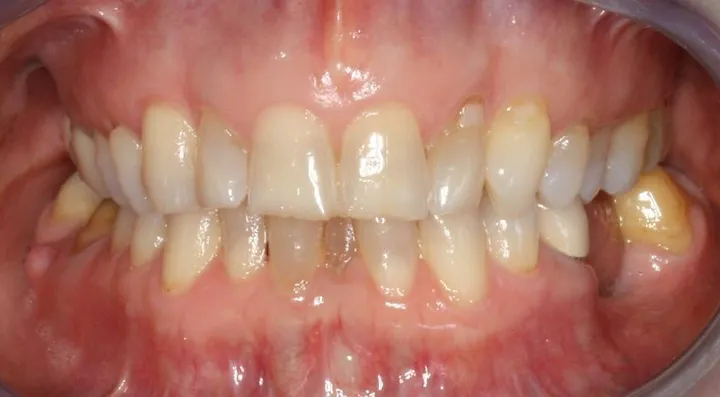

87f545_bc43680091984bbdb74de17eb337bbfd~mv2_d_1920_1280_s_2.webp

87f545_f42d29ecf80a4b9fa8b3f13471579528~mv2_d_1920_1280_s_2.webp

87f545_1c85956a5c2243d1acfc7176f18e69a7~mv2_d_1920_1280_s_2.webp

87f545_91b464f1d91749a39ae126d3341b6d30~mv2.webp

look how the maxilla was ripped apart on this one holy chit